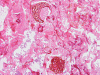

Pathology of the Case: Multiple tissue samples were from several locations of the sinuses were rerceived. The specimen was in the form of small aggregates of irregularly shaped, tan brown, necrotic debri with clotted blood and purulent material. Admixed with the soft tissue were small fragments of bone. Frozen section of “left nasal contents” reveals fungal organisms with hyphae and nonviable collagenous tissue, suspicious for invasive fungal infection. On permanent sections, about 99% of the tissue is composed of necrotic debri. There is an abundance of fungal organisms.  While some of the organisms are scattered, there are areas suggestive of an angioinvasive pattern. These organisms may well be recognized by hematoxylin and eosin stain but also well demonstrated by PAS and GMS stain. The organisms contain pauciseptate, “ribbon-like,” irregular hyphae with acute and right-angle branching. Associated with the hyphae are globus-shaped, pigmented sporangia  and columella (Panel C, D, and E). The hyphae are wide and here show acute angle branching. Occasional septum can be seen (Panel  D and E). The sporangium on the left shows angulated sporangiospores (Panel C and E). These features are characteristic of the class Zygomyycetes, order Mucorales. This order includes the Rhizopus and Mucor species. Fungal culture identified a Rhizopus specie as well as Aspergillus. The pathologic features are most compatible with a sino-nasal mixed fungal infection in an immunocompromised host.